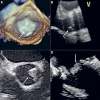

Transcatheter aortic valve implantation (TAVI) within failed bioprosthetic surgical aortic valves (valve-in-valve TAVI) has become an established procedure, currently approved for patients deemed at high risk for repeat aortic valve intervention. Although less invasive than surgical reoperation, challenges of valve-in-valve treatment include higher rates of malposition, prosthesis-patient mismatch and coronary obstruction. Thus, optimal patient selection and preprocedural planning is of the utmost importance to minimise the risk of these complications. In this review article we provide a fully illustrated overview of the most significant periprocedural operative considerations for valve-in-valve TAVI.